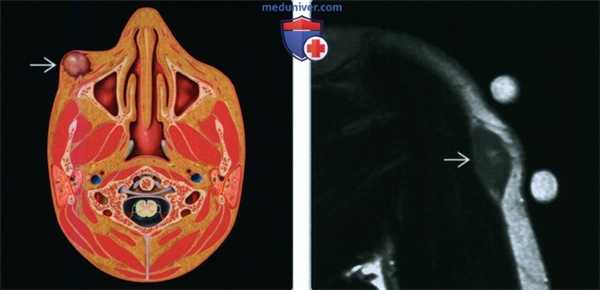

(Слева) Рисунок, аксиальный срез: образование в подкожной клетчатке лица. Голова и шея являются второй по частоте локализацией этих образований после конечностей.

(Справа) МРТ плеча, Т2ВИ, коронарный срез: определяется глубокая доброкачественная фиброзная гистиоцитома в подкожной клетчатке. Образование гетерогенно гиперинтенсивное по отношению к скелетным мышцам и имеет неспецифическую картину. В этом случае невозможно полностью исключить злокачественные опухоли мягких тканей; необходима биопсия.